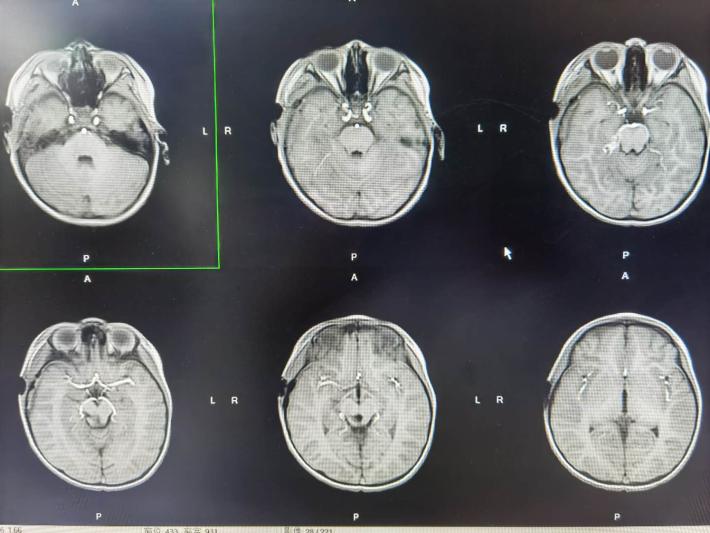

术前轴位

选择颞下入路,从侧方全切除肿瘤,没有选用枕下经小脑幕或幕下小脑上入路

脑干造瘘口控制在2-3毫米,全切除肿瘤并打通中脑导水管

术前轴位,可见肿瘤,用来对比术后轴位